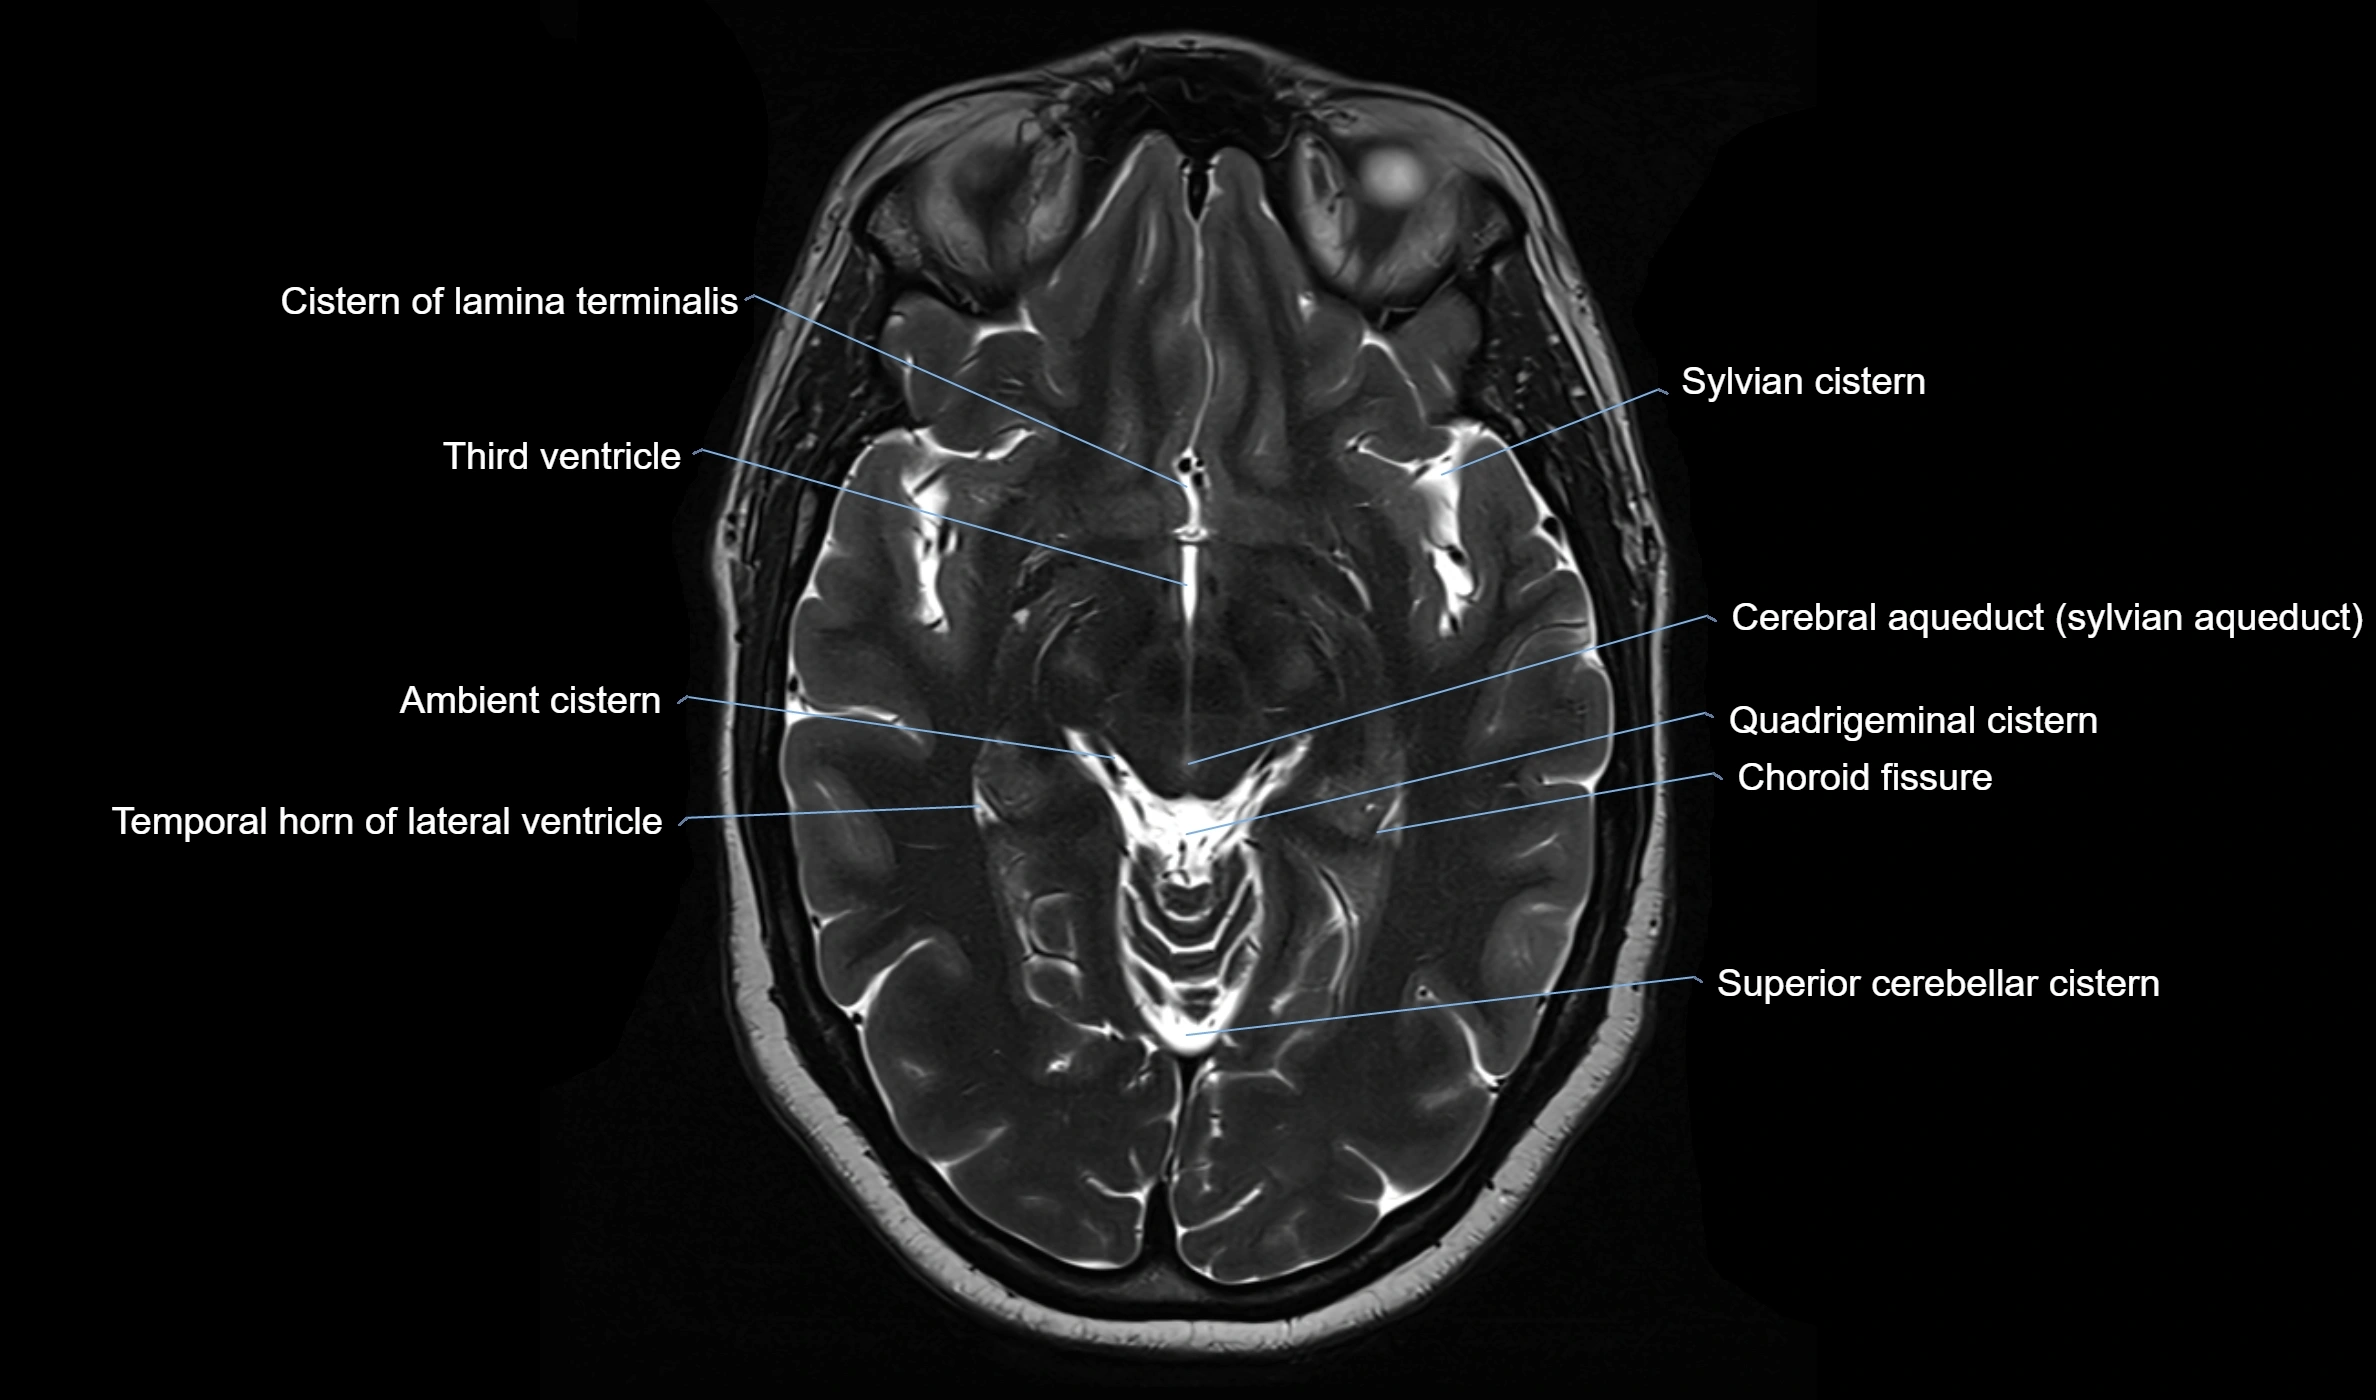

Ambient cistern

The ambient cistern is a paired, narrow, and elongated subarachnoid space located bilaterally along the lateral aspect of the midbrain. It serves as a conduit between the interpeduncular cistern anteriorly and the quadrigeminal cistern posteriorly. This cistern houses critical neurovascular structures, including parts of the posterior cerebral artery, superior cerebellar artery, trochlear nerve (cranial nerve IV), and the basal vein of Rosenthal. It plays an important role in the circulation of cerebrospinal fluid (CSF) and provides an anatomical corridor for various vessels and nerves passing around the midbrain.

• T2-weighted images:

• The cistern is hyperintense (bright) due to the high water content of CSF.

• Encapsulated vessels and nerves are seen as flow voids or hypointense lines within the bright background.